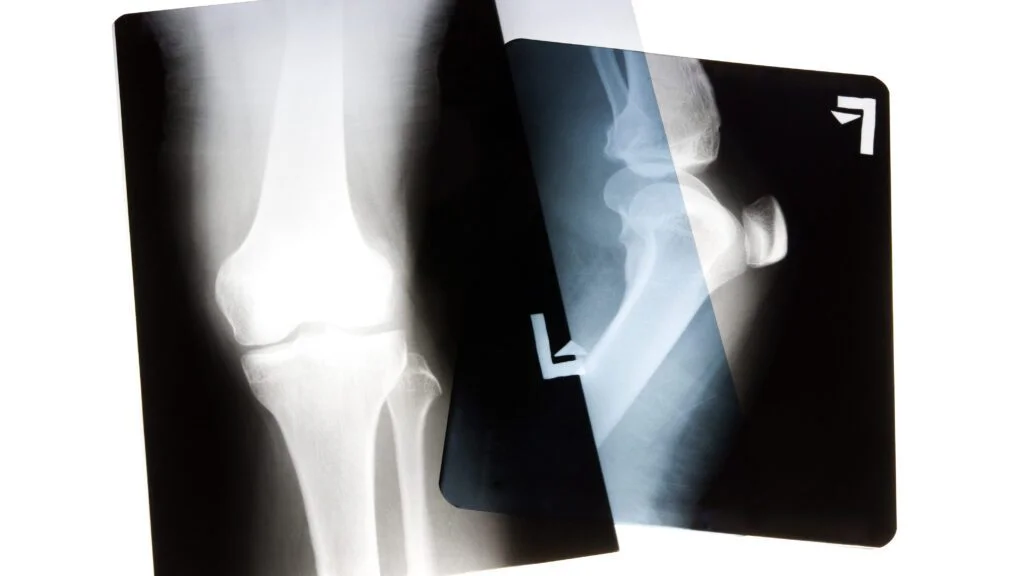

Vynálezy doprovázejí lidstvo po celou dobu jeho existence, neboť umožňují pokrok. Koncem 19. století nastaly obzvlášť přínosné časy, jelikož byla věnována velká pozornost fyzice. Otevřela se tak cesta k mnohem složitějším a převratnějším výzkumům. Jedním z nich byl Röntgenův objev rentgenových paprsků, čímž se výrazně posunula medicína.

Princip, který vedl k zavedení rentgenu, Wilhelm Röntgen objevil náhodou.